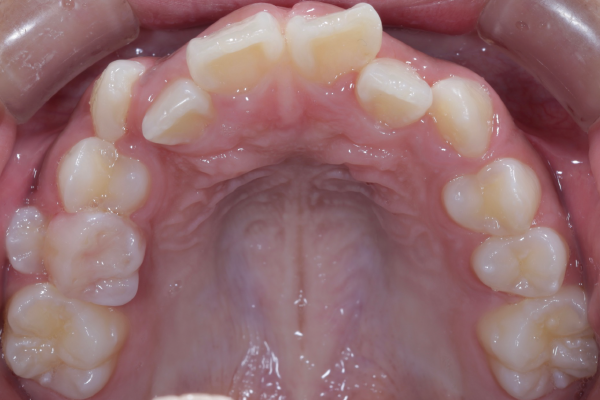

精密検査では、前歯部を中心とした叢生(歯の重なり)が確認され、現在だけでなく将来的な口腔環境も考慮した治療方針について詳しくご説明した上で、矯正治療を開始することとなりました。

患者様は10代の女性で、前歯を中心とした歯並びのガタつき(叢生)を気にされて来院されました。できるだけ抜歯をせずに矯正治療を行いたいというご希望があり、精密検査を実施しました。

検査の結果、歯列全体のスペースバランスを調整することで、抜歯を行わずに歯並びの改善が可能と判断しました。歯の移動量やコントロール性を考慮し、今回はワイヤー矯正を用いた治療計画をご提案し、患者様にも十分ご理解いただいた上で治療を開始しました。

【矯正治療開始11ヶ月】

11ヶ月経ち歯のガタガタが改善し、歯並びが綺麗になってきています。